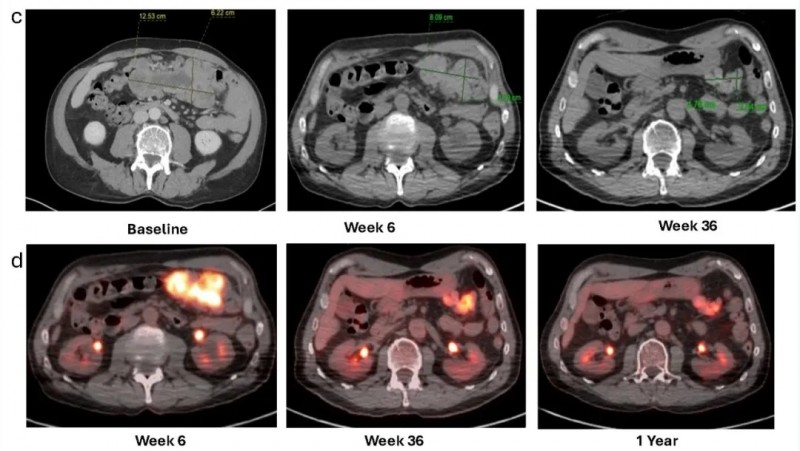

2025年11月17日,国际期刊《癌症免疫和免疫疗法》报道了一则振奋人心的案例:一名晚期黑色素瘤合并慢性淋巴细胞白血病/小淋巴细胞淋巴瘤(CLL/SLL)的患者,经肿瘤浸润淋巴细胞(TIL)治疗后,实现了放射学缓解与分子学完全缓解,为这类难治性患者的治疗提供了全新参考。

该患者为60余岁,2015年12月确诊下巴pT1a期皮肤黑色素瘤,经广泛切除术后随访至2021年2月,因颈部淋巴结肿大且细针穿刺活检(FNA)证实黑色素瘤复发,开启后续治疗。该患者先后经历了两次进展,并相继接受过帕博利珠单抗辅助治疗、伊匹木单抗+纳武利尤单抗、纳武利尤单抗联合替莫唑胺等治疗。后续考虑到患者无症状、CLL预后良好,且lifileucel已获FDA批准用于免疫检查点耐药性转移性黑色素瘤,最终决定采用lifileucel TIL方案治疗。

结果显示:根据实体瘤疗效评价标准(RECIST)v1.1,治疗6周后患者影像学表现达部分缓解(PR)。12个月随访时缓解持续,靶病灶缩小65%。PET/CT显示,治疗后6周~1年,代谢活性持续下降(详见下图c、d)。

▲图源“Front Immunol”,版权归原作者所有,如无意中侵犯了知识产权,请联系我们删除